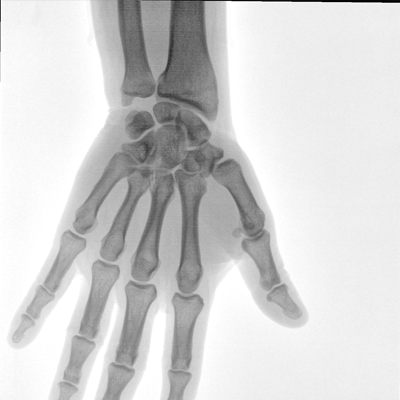

在球管和平板探测器两端,分别加装了激光定位系统,满足不同摆位无射线下的定位需求,降低医患辐射剂量的同时,提高临床工作效率。

具备束光器预览功能,可以在无射线状态下,实现曝光范围大小的调节;大幅减少临床反复曝光带来的射线辐射;并自动调整图像兴趣区大小与位置,使自动模式更准确。

滤线栅可插拔式设计符合行业标准,用于儿科和其他剂量敏感的临床应用,使用简便,保障图像清晰的同时,可有效防护辐射危害。